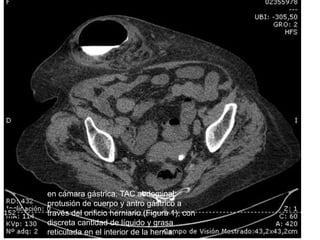

Imagen de TAC dinámica para

en cámara gástrica. TAC abdominal:

través del orificio herniario (Figura 1), con

discreta cantidad de líquido y grasa

reticulada en el interior de la hernia.